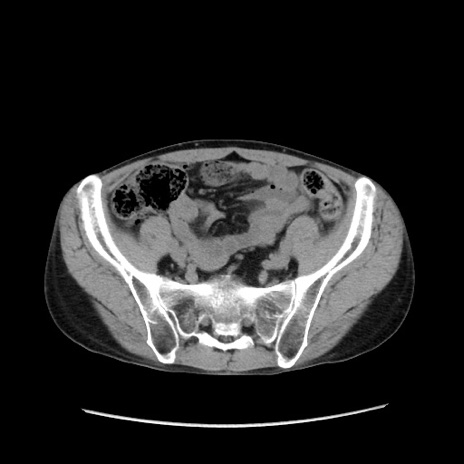

症例37(横断像)

【症例】40歳代 男性

【主訴】腹痛

【現病歴】4時間ほど前に電車に乗車中に臍部上より腹痛出現。徐々に増悪し起立困難となり、救急外来受診。生ものは数日食べていない。今朝お雑煮を食べた。

【身体所見】BT 36.8℃、BP 117/84mmHg、HR 91/min、SpO2 97%、苦悶様、腹部:臍上部広範囲圧痛あり、反跳痛±

【データ】WBC 8100、CRP 0.03